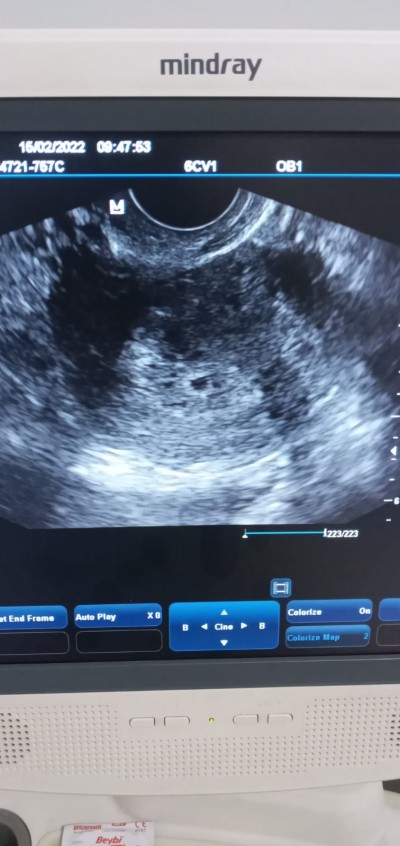

Resme bakın kızlar kaç haftalık bir ultrason görüntüsü sizce bu

Benim 5 haftalıkKen. Falan böyleydi sadece kese görünüyor

4 veya 5 haftalık